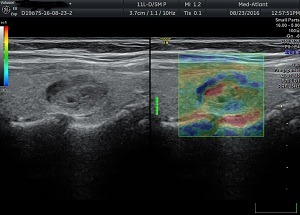

Обстеження проводиться за допомогою ультразвукового обладнання і спеціальних датчиків. На монітор лікарю виводиться еластограма, де різними кольорами позначається щільність тканин. Згідно шкали жорсткості кольорів та коефіцієнту strain ratio – що індивідуально розраховує контрольне значення деформації тканин, лікар робить опис і висновок.

За шкалою кольорів:

1.Синьо-зелений – тканини мають середню жорсткість, за подальшими змінами необхідно спостерігати або застосовувати додаткові методи діагностики (біопсія за показами).

2. Зелено-жовто-червоний колір – тканина низької жорсткості, що є показником доброякісного утворення.

3. Синій колір – є показником тканини високої жорсткості, що вказує на злоякісний характер утворення.